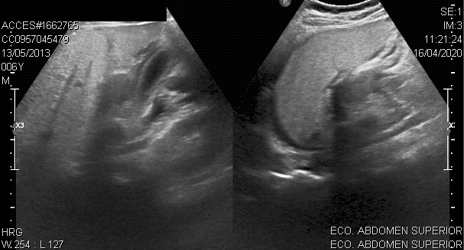

En la ecografía de abdomen realizada a 24 pacientes se encontró el mismo hallazgo en 5 casos (figura 3).

Cabe mencionar que ante la duda diagnóstica tanto del pediatra en primera línea como del cirujano pediatra, se realizó estudios de imágenes complementarios tales como ecografía o tomografía de abdomen en determinados pacientes. El principal hallazgo de estas ayudas diagnósticas fueron las alteraciones perivesiculares en el 30% de los casos. Razón por la que sugerimos que ante pacientes con sospecha clínica de apendicitis que presenten clínica o nexo epidemiológico de COVID-19 se considere realizar TAC de abdomen previo al procedimiento. Una revisión sistemática previamente ha reportado que hasta un 34% de los pacientes pediátricos no presentaron ningún hallazgo en tomografía de tórax [18], mientras que en este estudio todos los pacientes mostraron diferentes alteraciones en la imagen pulmonar como se mencionó en los resultados, lo cual podría estar relacionado a las complicaciones que desarrollaron estos pacientes ya sea desde el momento de su ingreso hospitalario o durante la estancia en el mismo.